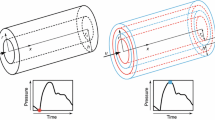

Calculation of Pulse Wave Velocity and Total Arterial Compliance

Aortic pulse wave velocity (aPWV) was estimated by determining the transit time via pulse wave analysis, similarly to the in vivo methodologies for aPWV measurement.12 The transit time between proximal and distal pressure waveforms was determined with an automated technique that located the minimum diastolic pressure in the waveform.5 The waveforms were recorded at arterial sites that resemble aPWV measurement in clinical practice; namely, the carotid and femoral artery (carotid-to-femoral PWV), as previously described,12,34 and shown schematically in Fig. 1 (Sites A and B, respectively). The “real” C T for each of the 1000 simulated cases, was directly calculated as the summation of volumetric compliance for all the arterial segments (at mean pressure), including the compliance of the terminal sites (Windkessel models). The resulting values of total compliance ranged between 0.126 and 2.256 mL/mmHg. Peripheral resistance had a minimum of 0.600 mmHg s/mL and a maximum of 1.681 mmHg s/mL. The computed C T and aPWV values were fitted according to the nonlinear power relationship given by Eq. (5). The following fit quality parameters were calculated: sum of square errors (SSE) R 2, and root mean square error (RMSE).

Nature of the Generalized Bramwell–Hill Law and Physiological Significance of Its Parameters

Senso stricto, the Bramwell–Hill equation is applied to derive local PWV from local area compliance (PWV = (A/ρ*1/C A)1/2). Neglecting tapering and multiplying local cross-sectional area, A, and local area compliance, C A, by the length of the arterial segment under consideration, we may express segment volume compliance as a function of average PWV in the same segment. Summing up the compliance in all arterial segments we derive the generalized Bramwell–Hill law expressed in Eq. (3). We went further to express this generalized Bramwell–Hill equation in terms of a clinically relevant aortic PWV, such as the carotid-to-femoral PWV. This gave rise to a generalized Bramwell–Hill equation with a single coefficient k, whose analytical form is given in Eq. (4). The coefficient k is principally dependent on geometry and, in specific, on the weighted sum of all arterial segment volumes. The weighting coefficient of each segment volume is \( 1 /\rho *\left( {{\text{aPWV}}^{ 2} / {\text{PWV}}_{i}^{2} } \right), \) with the ratio aPWV/PWV i being quite comparable between individuals. Figure 4 shows the fit curves that were calculated for three subgroups based on the geometry change that was performed. There was a very good agreement regarding the proportionality of the k values to the volume of the arterial tree. The 10% increase of the arterial cross-sectional areas (and subsequently volume) resulted in an 11.8% increase in the value of k, whereas 10% volume decrease resulted in a 10.8% decrease for the power relationship constant. Hence, overall, we expect coefficient k to be principally body size dependent, but this needs to be verified with further studies either in silico or with in vivo measurements.